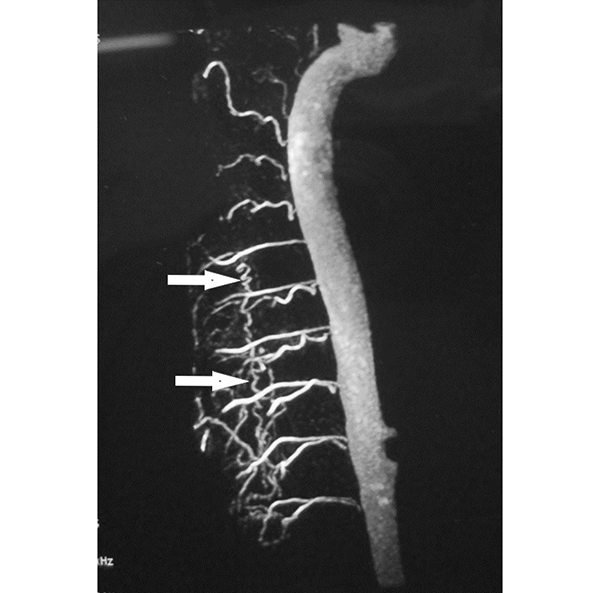

Figura 5: Caso #1. ADM mostrando la FDAVE en D8 izq. antes y después de la embolización. En la imagen de la izquierda (pre-embolización) las flechas blancas muestran la vena de drenaje de la FDAVE desde el punto fistuloso (más lateral) hacia medial en forma descendente y llegando a la línea media en donde se anastomosa con la vena espinal posterior y continúa hacia abajo en forma serpiginosa. La foto de la derecha (post-embolización) dejó de observarse la vena de drenaje y la vena espinal posterior (oclusión total de la FDAVE).

Figura 6: Caso #1. FDAVE recanalizada a los 15 meses post-embolización. ADM de frente (izquierda) y de perfil (derecha) las flechas blancas muestran el trayecto ascendente de la vena de drenaje. En el perfil se observa además que la vena de drenaje es dorsal.